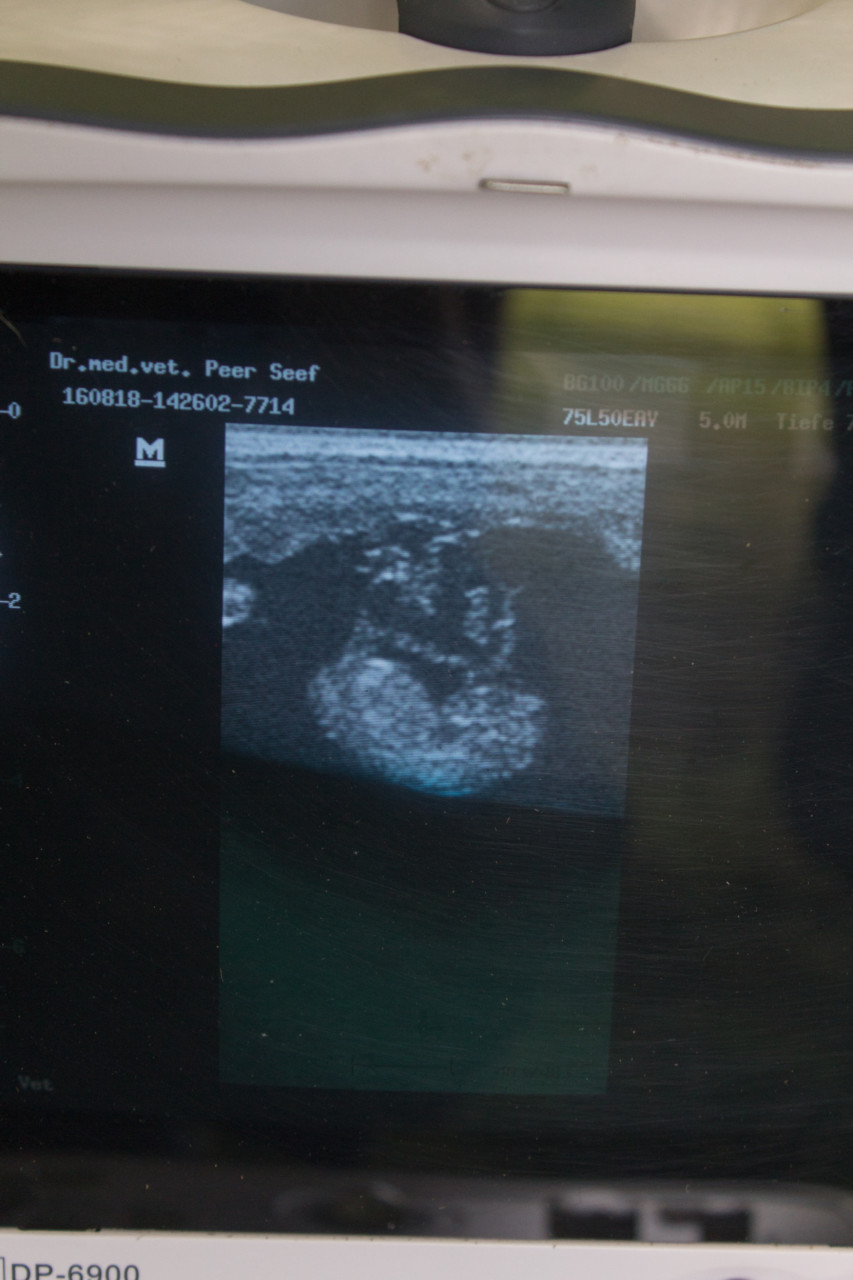

Meine Leistungen für Ihr Tier